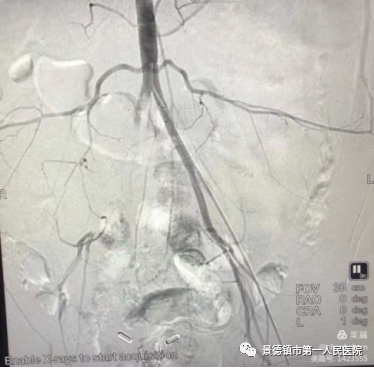

从无到有:部分血管疾病患者再也不用辗转去大城市求医       2018年4月,市一院了解到我市在血管疾病方面的空白与短板后欲组建专门的血管外科,于是如今的血管外科负责人张善忠与万冰受命前往北京学习。张善忠是普外科副主任,从医数十载,有着丰富地临床经验,他与万冰在2018年4月一同前往北京学习先进地血管外科的技术,历时数月学习后在2018年底组建队伍成立血管外科。       市一院血管外科成立后2019年共收治了16名主动脉夹层患者,16名患者无人死亡。要知道,目前已知的许多血管疾病多为突发性疾病,来势汹汹且死亡率高,市一院成立血管外科以前,许多血管疾病患者,只能送往其他城市求医,由于血管疾病的凶险,这些患者中有的病故于求医途中。而在市一院血管外科成立后,2019年收治的16名主动脉夹层病患,由于得到了及时地治疗,无一人死亡。       2021年1月,市一院血管外科便收治了1名血管疾病患者,该患者今年已经80岁,张善忠诊断其患有髂总动脉瘤,该动脉瘤约4.4~4.5公分。张善忠1月30日为其进行微创手术,手术效果较好,该患者在2月4日便办理了出院。出院时该患者与其家人不停地对张善忠表示感谢,并对其医术赞不绝口。 刻不容缓:血管外科是与病魔争分夺秒斗争的战场       许多人对于血管外科疾病不甚了解,有时无法因为无法判断自己身患何病而延误病情。       2019年下半年,张善忠收治了一位因对血管疾病不甚了解而险些截肢的患者。当时该患者整条腿剧烈疼痛,在首次求医时医生初诊为坐骨神经痛。2日后该患者不堪忍受疼痛辗转来到市一院求医,当时张善忠一看到这名患者整条腿疼痛难忍,再看到他的腿部皮肤因缺血呈青紫色,便判断有可能是股动脉栓塞,通过各项检查,得出自己的判断正确,张善忠立即手术将血管内的栓塞取出,保住了患者的腿。他说:“许多市民对血管疾病不了解当成一般的疾病治疗,甚至有些抱着侥幸的念头,觉得多休息就好,但这样的想法往往会延误最佳的治疗时机,比如这位股动脉栓塞的患者,要是再耽搁下去,说不定就要截肢。”       张善忠表示,血管疾病非常危险,其临床表现与一般病症的区别是血管疾病的患者往往会感觉到病灶部位的剧烈疼痛,如果出现这一症状,一定要及时就医,以免延误最佳治疗时机。同时张善忠希望提醒广大市民,如今血管类疾病患者年龄越来越年轻化,与许多人心中的固有印象不同,如今的患者中有许多只有40岁左右。因此希望广大市民在日常生活中注意饮食健康,尤其是需要长期保持同一姿势的市民,在日常生活中需要加强锻炼,预防血管疾病的发生。(稿件来源于瓷都晚报)